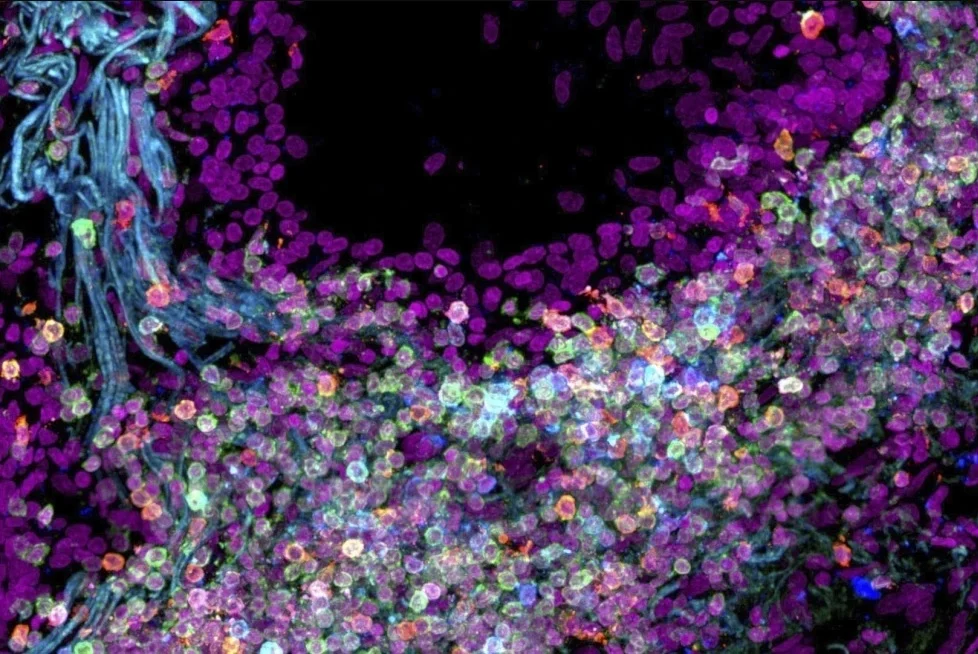

Científicos crean mapa del cuerpo humano célula por célula

Ayudará a conocer mejor las funciones de estas unidades morfológicas y entender enfermedades como el cáncer.

Investigadores han creado un mapa preliminar de algunas de las cerca de 37,2 billones de células en el cuerpo humano.

Cada tipo de célula tiene un papel específico, y conocer lo que hace cada una de ellas puede ayudar a los científicos a tener un mejor entendimiento sobre la salud y enfermedades como el cáncer.

Los científicos se enfocaron en ciertos órganos —esquematizando las funciones de las células en la boca, el estómago y los intestinos, así como en las células que determinan la manera en que se desarrollan los huesos y articulaciones. También analizaron cuáles son las células que se agrupan en los tejidos, dónde se ubican dentro del cuerpo, y cómo cambian con el paso del tiempo.

Esperan que el atlas de alta resolución —considerado un primer borrador— ayude a los investigadores a combatir enfermedades que dañan o corrompen a las células humanas.

El mapa celular actual no solo traza los distintos tipos de células humanas, sino que también muestra las relaciones que tienen las células entre sí, dijo el doctor Timothy Chan, un experto en cáncer de la Cleveland Clinic.